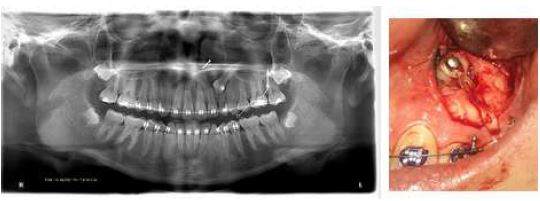

This is a 15-year-old female patient who attended a private clinic for orthodontic treatment. No alterations were described in the clinical records and systems review. Extraoral examination revealed a mesoprosopic-type face with a straight profile, adequate lip seal and facial symmetry. Intraoral examination revealed a Class II occlusal relationship, left subdivision, lower midline shifted 2 mm to the left, 40 % overbite, 3 mm overjet, presence of tooth 63 (FDI World Dental Federation -ISO- notation), moderate anterior-inferior crowding, and oval arches (Figure 2).

In the radiographic analysis, the orthopantomography (Figure 2) indicates, according to the Ericson and Kurol classification, that the crown of 23, mesodistal, was located in sector 4; In addition, the angle of the longitudinal axis of tooth 23 with the midline had a value of 50 °, which increased the risk of resorption of the lateral incisor (10) by 50 %, which is evident in the radiograph (Figure 2).

Initial Records Photography, Orthopantomography and Cone Beam Tomography, Case 1

FIGURE 2

The initial cone beam tomography shows 3D reconstruction, cuts in the different planes of tooth 23 and its relationship with 22 and 21, in which root resorption is evident. Source: the authors with permission from the patient.

Cone beam tomography analysis (Figure 2) showed moderate impaction of tooth 23 in the buccal position, whose coronal portion was close to the apical third of 21 and 22 with remodeling of the apical third of tooth 22. In Steiner's cephalometric analysis, anteroposterior and vertical assessment angles were adequate, resulting in a skeletal class I and neutral growth pattern.